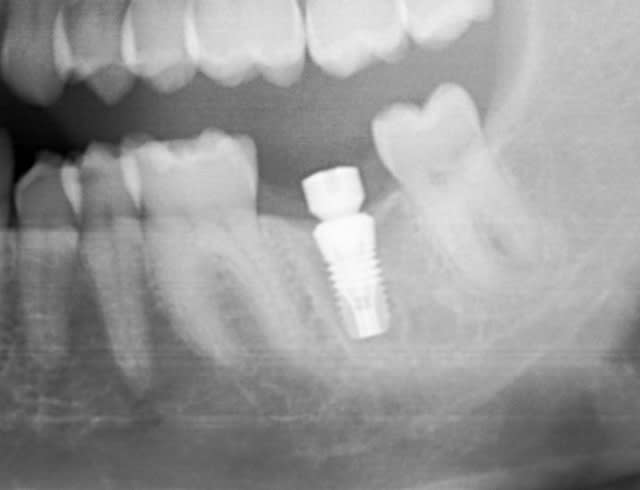

bon les pièces jointes d'alhoun.

décidément aussi nul en endo qu'en internet, et ton implant il est de traviole;)

dans la même philosophie de connectique

Easyimplant mjxotp - Eugenol

Rvg easy briwxo - Eugenol

Ok j'ai compris. Par contre, sur la radio l'implant a l'air d'être conique sur toute sa hauteur, c'est une illusion d'optique où il est vraiment comme ça, je ne le vois pas sur le site d'Astra ?

tu parles de celui de growler?

c'est normal c'est pas un astra, c'est un easy implant, mais il est pas conique tout le long il me semble.

çà doit être une déformation du cliché, regardes bien le premier cliché avec le pilier de cicatisation: on voit bien la partie cylindrique puis l'évasement.